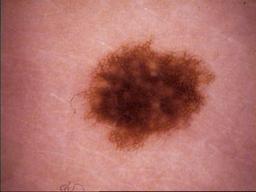

{

"age_approx": 35,

"anatom_site_general": "lower extremity",

"concomitant_biopsy": false,

"diagnosis_1": "Benign",

"diagnosis_2": "Benign melanocytic proliferations",

"diagnosis_3": "Nevus",

"diagnosis_4": "Nevus, NOS, Compound",

"diagnosis_confirm_type": "serial imaging showing no change",

"image_type": "dermoscopic",

"melanocytic": true,

"patient_id": "IP_5370468",

"sex": "male"